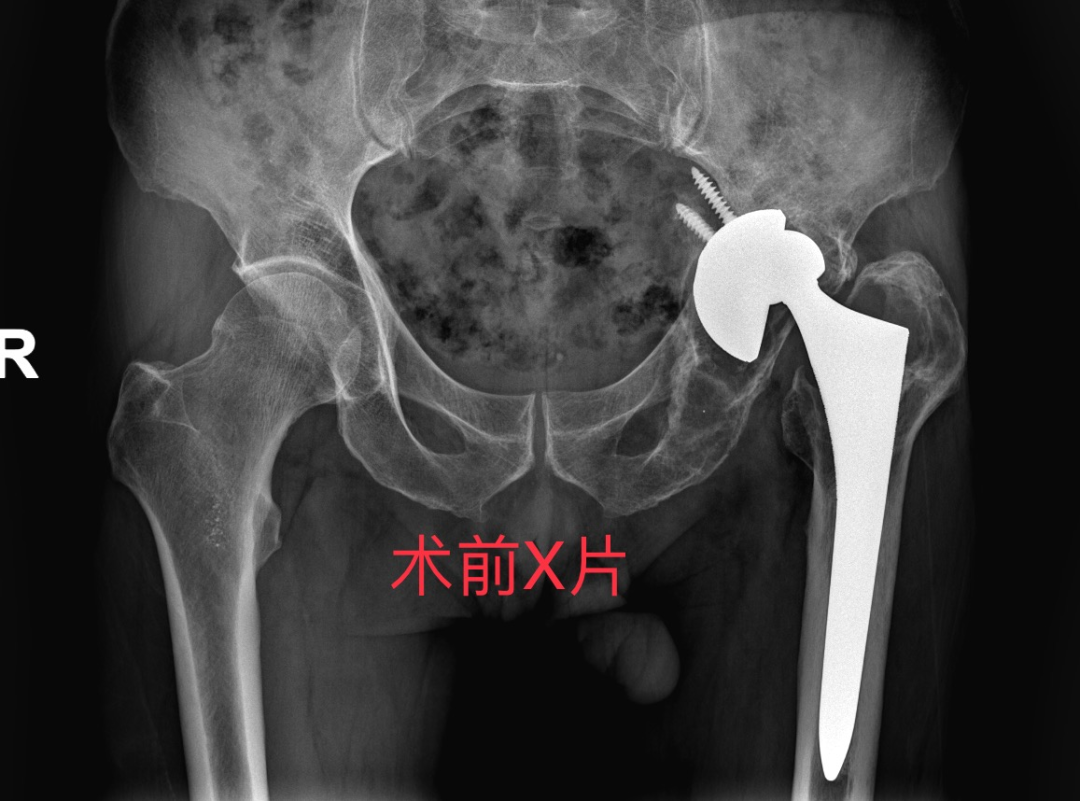

曾爷爷是一名74岁的老年男性患者,15年前因“左侧股骨头缺血性坏死”于我院骨伤科行“左侧人工全髋关节置换术”,术后康复出院。

3个月前因摔伤,导致人工髋关节假体松动、髋臼骨折、大面积骨溶解,长期卧床、生活不能自理,辗转多家医院未能得到有效治疗,不得不从外地专程赶往我院骨伤中心(关节-运动医学科)住院治疗。

入院后完善DR及CT检查后,诊断为:

1.左侧人工全髋关节置换术后假体松动

2.左侧髋臼骨缺损(PaproskyIIIB型)

3.骨质疏松

4.左髋部骨囊肿、局限积液

根据患者病情,考虑常规人工髋关节假体无法实现有效初始稳定性,而 3D 打印定制假体,能“量体裁衣” 般精准设计,突破常规手术局限,为曾爷爷量身打造独一无二的治疗方案,故选择3D打印个体化定制假体进行全髋关节翻修术。

通过X片、CT等评估骨缺损程度(如Paprosky分型),指导个性化方案设计。